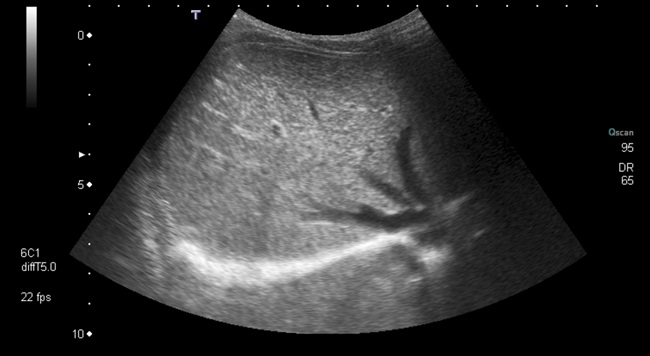

Varón de seis meses, con antecedente de ingreso en la Unidad de Neonatología por prematuridad, que derivan a consulta de Digestivo Infantil por sospecha de agenesia de vesícula biliar visualizada desde la ecografía prenatal de la semana 22. Durante el ingreso en el periodo neonatal se realizan varias analíticas sanguíneas con perfil hepático sin observarse alteraciones y dos ecografías abdominales (a los 10 y a los 28 días de vida) donde no se identifica vesícula (Fig. 1).

| Figura 1. Ecografía hepática: hígado homogéneo de tamaño normal sin lesiones focales. Ausencia de vesícula. No dilatación de la vía biliar intra- y extrahepática |

Se revisa al paciente a los seis meses y a los tres años de edad con analítica y ecografía abdominal compatibles con diagnóstico de agenesia de la vesícula biliar. Asintomático, con exploración física sin alteraciones y buena ganancia de peso y talla en todo momento.